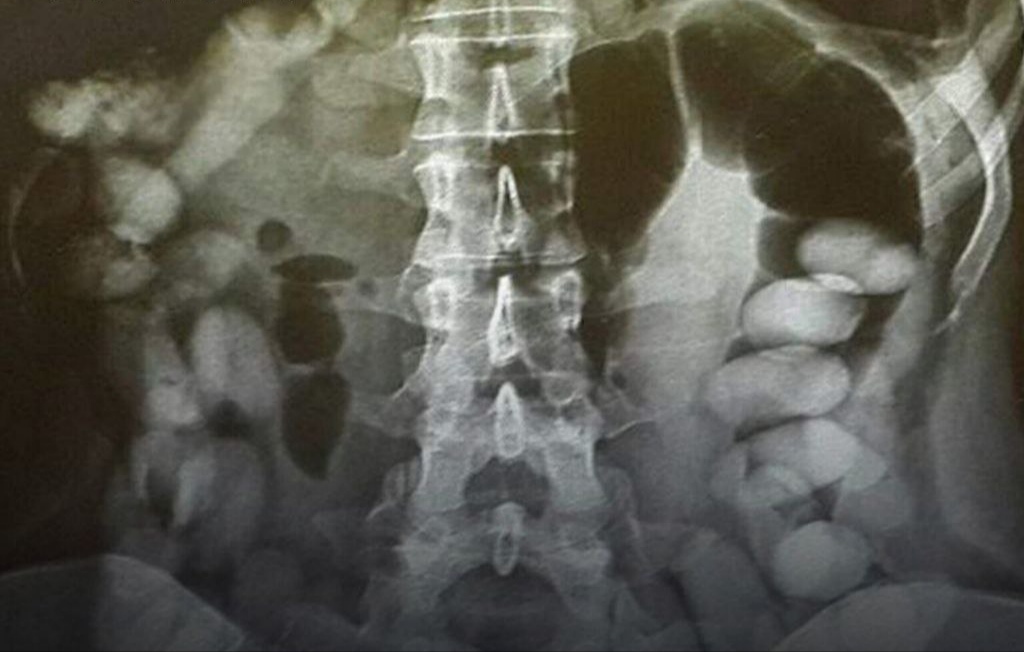

کن نیوز| کارکنان پلیس حین کنترل و بازرسی مسافرین پرواز ورودی از یکی‌ از کشورهای خارجی، در رابطه با حمل مواد مخدر مظنون شدند. در بازرسی فنی و پس از انجام آزمایشات، محرز شد مواد مخدر به صورت حرفه‌ای آب‌بندی شده و کاملا قابل رویت است، خود متهم نیز در خصوص بلع مواد مخدر بسته‌بندی شده اعتراف کرد که در نهایت ضمن هماهنگی قضایی و مراقبت های ویژه، تعداد ۷۷ بسته مواد مخدر از نوع کوکائین به‌صورت آب‌بندی شده به وزن ۹۴۷ گرم از وی دفع و ضبط شد که طبق نظر کارشناسی ارزش ریالی این مواد مکشوفه بالغ بر ۵۰ میلیارد ریال برآورد شد.